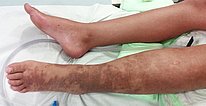

Female patient 8 years of age at the time, with elongated left leg (leg length discrepancy +1.8 cm), which is always significantly warmer than the right leg. In the left lower leg, ankle and foot there is permanent slight edema, here in the form of phlebedema due to the increased venous pressure with extensive arteriovenous fistulas of the entire left lower extremity. Purpura jaune d'ocre as deposits of erythrocytes in the skin due to red blood cells being squeezed out in chronic venous hypertension.

The marked phlebedema of the left leg with swelling in the distal region in chronic venous hypertension due to the multiple arteriovenous fistulas is clearly seen when comparing sides.

The picture at 12 years of age shows progression of both skin manifestations and edema. Owing to the accompanying progressive hyperplasia of the left lower extremity, it also appears significantly larger than the right side in terms of soft tissue.

Photograph now in the 13th year of life. The edema is somewhat less pronounced after the embolizations because the venous pressure is lower. Nevertheless, the purpura jaune d'ocre has increased. Its color change is also typical, from proximally paler and redder to distally darker and more color-intensive due to the distally higher hydrostatic pressure, which leads to more erythrocytes being squeezed out of the venous system.